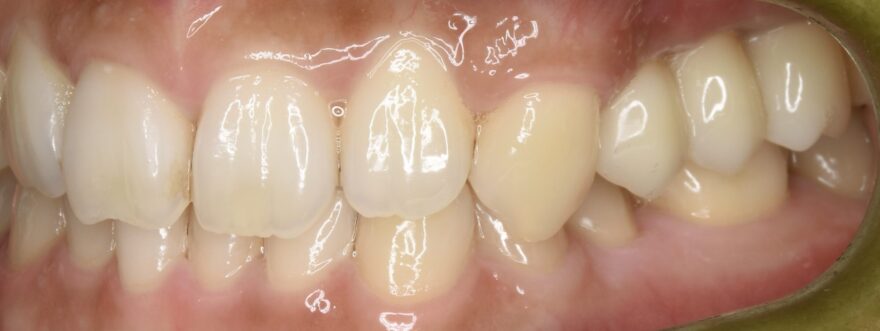

初診時の口腔内写真

治療後のレントゲン写真

大掛かりな骨を増やす手術を避け、治療期間の短縮をはかっても、インプラントは骨と結合しています。

治療後の口腔内写真